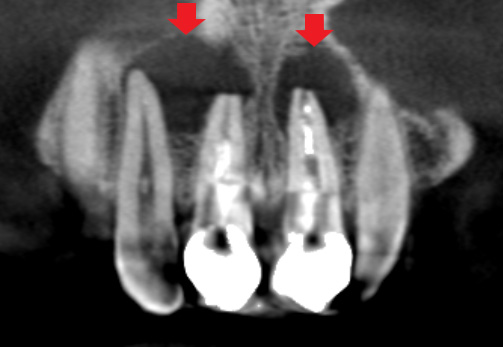

初診時のCT画像です。

矢印の先の黒い影が膿です。膿の大きさは、隣の歯の根に達するほどの大きな膿でした。